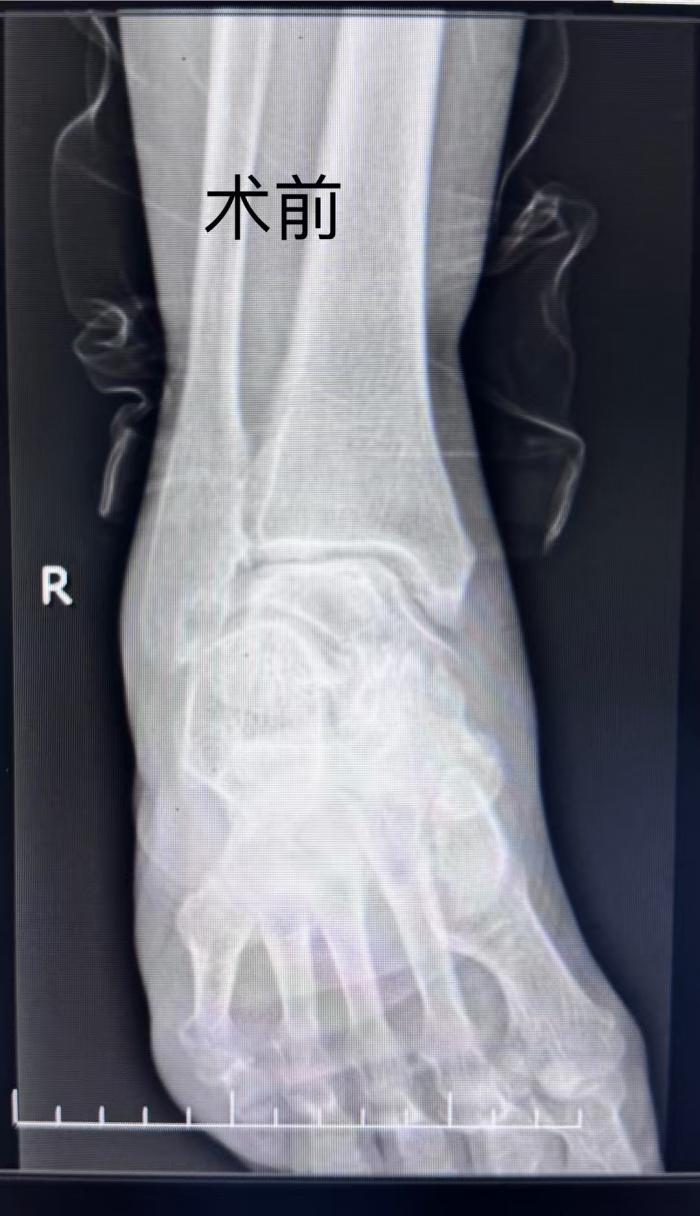

此次就诊的契机,源于欧阳阿姨的老伴因不慎摔伤导致股骨颈骨折,在湘南学院附属医院住院治疗。欧阳阿姨在病房照顾期间,骨一科主任唐新文注意到她走路一瘸一拐,询问情况并进行查体后,立即安排了右踝关节DR检查,最终以“右踝关节骨关节炎”将其收入科室治疗。

![]()